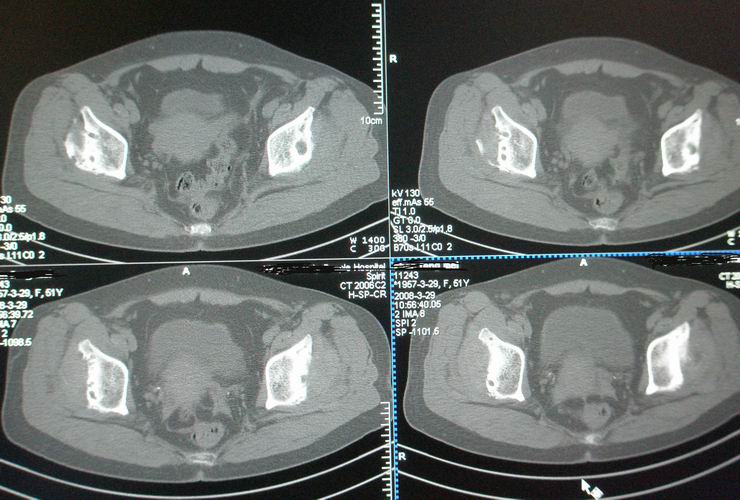

标题: CT12535:女,51岁.双髋痛多年,近加重,左腿难伸直. [打印本页]

标题: CT12535:女,51岁.双髋痛多年,近加重,左腿难伸直.

双髋无菌坏死(重度)??

先天性髋臼发育不良性骨病。双侧股骨头改变为继发性退变。

成人髋臼发育不良性骨关节病.是由于髋臼先天发育不良、髋臼角变大,部分股骨头位于髋臼以外,持重部位少,长期站立、负重造成髋臼退行性骨关节病,主要x线表现是:髋臼变浅平,髋臼角增大,ce角小于30度,髋关节骨性关节面增生硬化,关节间隙变窄,髋臼及股骨头可有囊变.但股骨头变形轻微,与股骨头坏死相比,预后好,可两三年变化不大,而股骨头坏死早期关节间隙不窄或增宽,等到间隙变窄时股骨头已明显变形.

鉴别:股骨头缺血坏死

双侧髋关节退行性骨关节病

(双侧股骨头变形明显,但坏死、囊变不明显)

双侧股骨头坏死!继发性退变。

既然双髋疼痛多年,不会是第一次检查吧,病人以前的诊断资料能否提供,病人的其他关节都正常吗?有没有东北地区居住史?首先考虑成人股骨头无菌坏死ⅴ期,其次要考虑大骨节病。

此病人从未看过病.家穷,临床医生要她做了椎间盘,未发现明显异常.我免费给她做了双髋.是南方人.十几年前痛过,自行贴膏药,开始自我感觉还好后来不行.近两年痛加重.下登困难.左腿不能伸直.